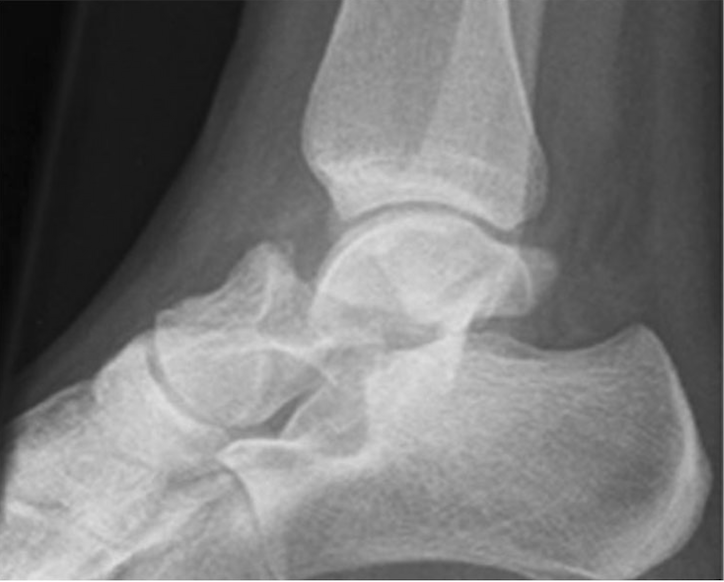

Talus fractures may involve different regions of the bone, including the talus neck, body, head, or lateral process, each with distinct injury patterns and treatment considerations. Even fractures that appear minimally displaced on initial imaging can have significant implications due to the importance of precise joint alignment and blood flow.

Imaging is essential for accurate diagnosis. X-rays are used initially, but CT scans are frequently obtained to define fracture patterns, displacement, and joint involvement. MRI may be considered in select cases to assess cartilage injury or blood supply to the talus.